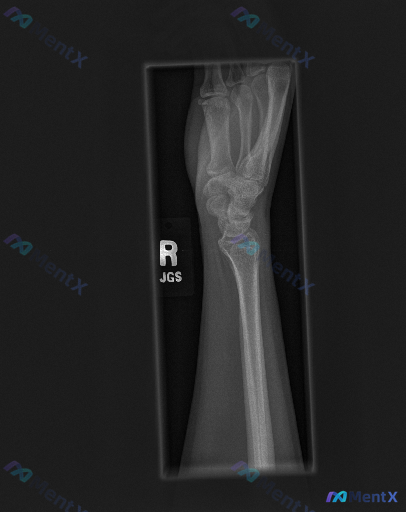

整理到一组右侧腕关节的影像与评估: - 影像:右侧腕关节侧位X光片 - 影像描述:投照体位基本标准,曝光适中;腕骨排列连续,月骨头状骨轴线对齐,未见明显骨折线、皮质中断或脱位;骨质密度均匀,无明显骨质疏松或破坏;桡腕、腕中关节间隙清晰;软组织影轮廓清晰,未见明显肿胀或脂肪垫移位;未见游离骨块、异物或...